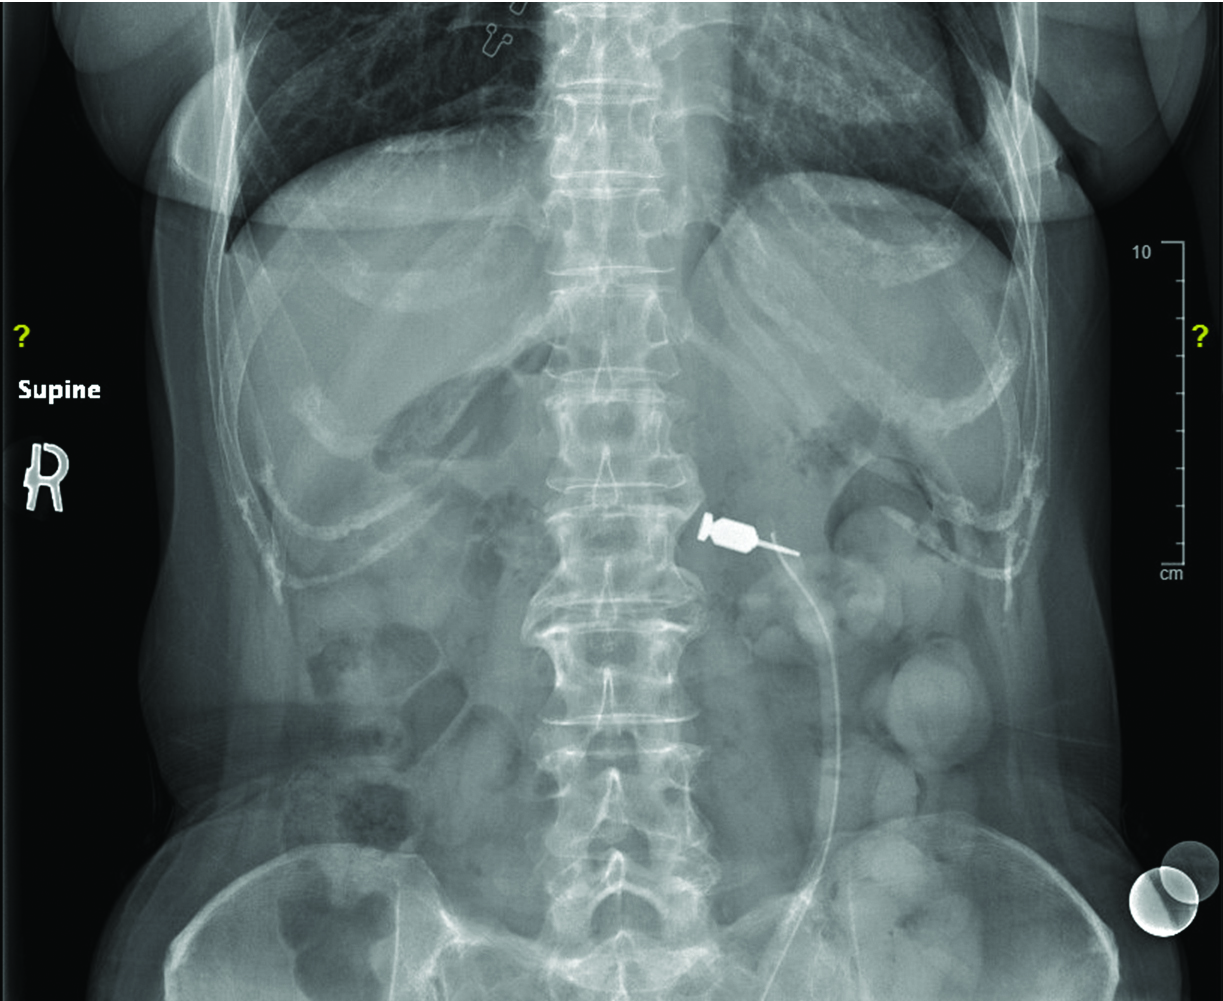

Figure 1 illustrates a patient with an abutment driver lodged in the fundus. During an attempt to endoscopically remove the abutment driver, the esophagus was perforated, resulting in the need for open surgery to repair the perforation. The patient required several days in the intensive care unit and a prolonged hospital stay.

Fig 1. An abutment driver has been lodged in the patient’s fundus. An attempt to endoscopically remove the dental instrument resulted in the esophagus being perforated, leading to open surgery to repair the perforation.

Figure 1